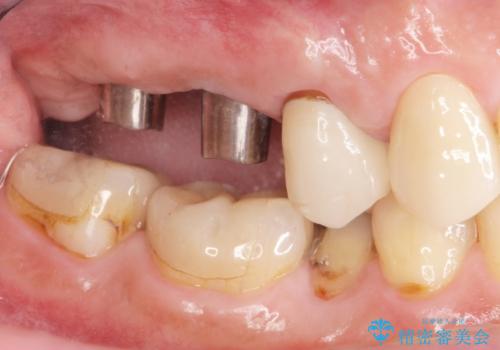

欠損した奥歯 インプラント補綴

- 歯が抜けてしまい、噛めなくなった右側奥歯の治療を希望され来院されました。

しっかりと咬合機能の回復をするためにインプラント治療を選択されました。

より清掃性の高い、チタン製カスタムアバットメント、審美製・強度に優れるジルコニアインプラントを用いたインプラント治療を計画します。

- 88万円(インプラント×2・チタンカスタムアバットメント×2・ジルコニアクラウン×2・仮歯×2)費用は治療当時の料金となります